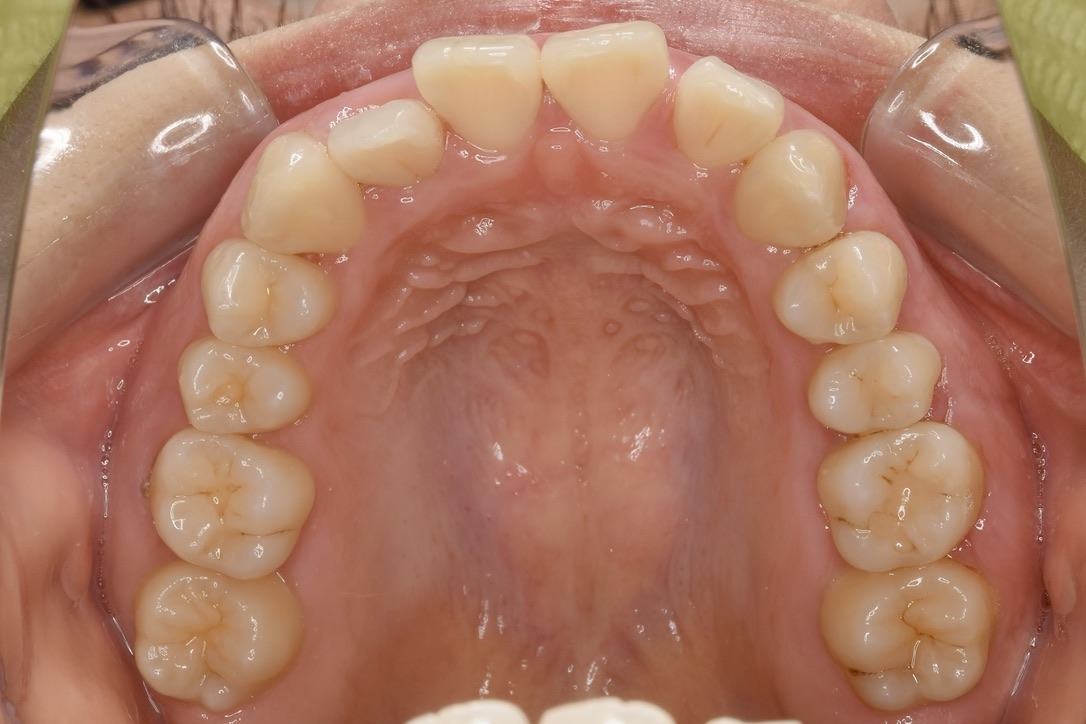

21歳 女性 治療期間:1年1ヶ月

叢生(ガタガタ)

マウスピース矯正装置(インビザライン)

BEFORE

AFTER

診断名・主な症状

叢生

治療内容

上下とも歯並びの横幅を広げながら、でこぼこを解消しました。

マウスピース矯正(インビザライン)

抜歯あり(智歯抜歯)

1年1ヶ月

10回

85万円程度(税別)

リスク・副作用

痛み、歯肉退縮、歯根吸収、抜歯に伴う出血や腫れが生じることがあります。